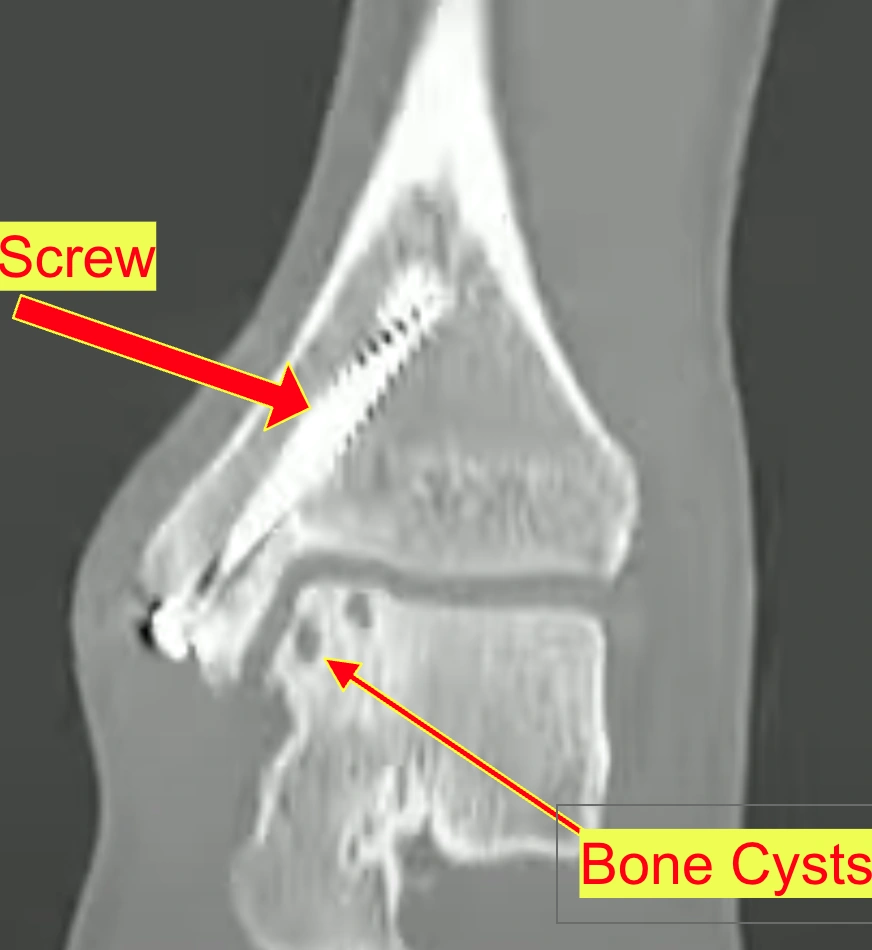

CT Review

• Fairly good incorporation of the medial shoulder talar allograft

→ The donor bone graft has mostly fused well

• Slight lucency on the most inferior aspect

→ Small gap/dark line visible at the bottom of the graft

• Mismatch in height with the graft sitting slightly proud (not universal)

→ The graft sticks up slightly higher than surrounding bone in some spots

• Significant cystic changes within the graft without obvious collapse

→ Fluid-filled pockets inside the graft, but it hasn't caved in

• Medial malleoli osteotomy healed with anatomic alignment and stable hardware

→ The bone that was cut to access the ankle has healed perfectly; screws are solid

• No significant arthritic changes adjacent to the osteotomy

→ No arthritis forming around where the bone was cut

• Mild anterior tibial and dorsal talar neck spurring, consistent with activities and possibly early arthritis

→ Small bone spurs forming at the front of the ankle, common with sports but could signal early arthritis

CT Scan Review

Dr. Gentile reviews the CT scan and explains the current state of the graft:

• Graft location: The original cut where the block of bone was removed and the donor bone placed is visible on the scan

• Graft incorporation: The donor bone incorporated well into the surrounding normal bone

• Cystic changes: Over time, the cartilage over the graft has likely thinned and broken down, allowing joint fluid to seep in and form cysts (like "Swiss cheese" or geodes)

• Pain source: When fluid pushes into these cysts, it creates pressure inside the bone which can cause pain. Additionally, if the cartilage surface has worn away, you may be rubbing on raw bone

• Graft alignment: Part of the graft may have healed sitting slightly high ("proud"), which means it hasn't been able to wear evenly over time — this happens more often than expected

• Graft size: The graft covers almost a third of the side of the talar bone — it's a sizable area

• Unknown factors: Can't determine from CT how much of the original smooth cartilage surface on the graft has survived vs. worn away

• Treatment approach: Depends on how much the symptoms bother you — can be approached conservatively or surgically

CT Scan Findings

Radiologist notes Plain-English explanation

Bones

• 15 mm area of sclerosis of medial talar dome with several subchondral cysts measuring up to 4 mm

→ There's a ~15mm dense/hardened spot on the inner ankle bone with small fluid-filled pockets underneath

• Consistent with incorporation of allograft with subsequent degenerative changes

→ The donor bone graft has fused in, but there's some wear and tear happening

• Linear lucency at presumed inferior margin of graft

→ There's a thin dark line at the bottom edge of the graft (could be a gap or incomplete fusion)

• Post-operative changes of ORIF of medial distal tibia with two screws; no residual fracture plane visualized

→ The two screws from surgery are visible; the bone they fixed has healed completely